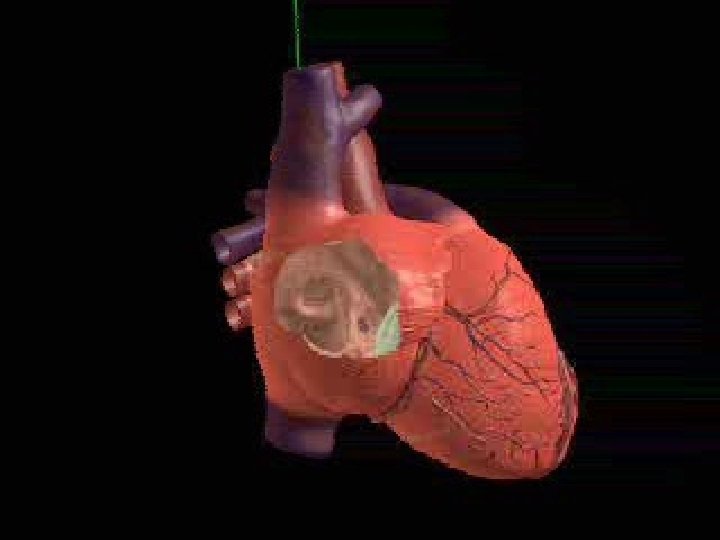

Obbiettivi della CRT Ottimizzare il ritardo AV per migliorare il riempimento diastolico ventricolare e ridurre il rigurgito mitralico diastolico Annullare o Ottimizzare il ritardo interventricolare ed intraventricolare, migliorando l’ asinergia di contrazione tra i 2 ventricolari e tra le pareti settali, laterale e posteriore (cordinando e anticipando la contrazione di esse, e la chiusura dei papillari) Migliorare la gittata cardiaca. ECG depicting interventricular conduction delay (IVCD) ECG depicting cardiac resynchronization Overview of Device Therapy 51